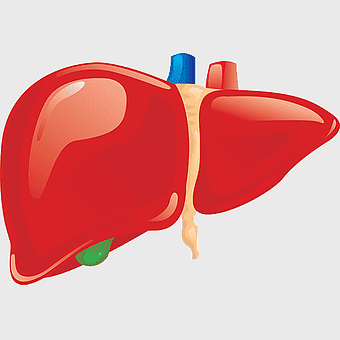

liver with gallbladder diagram, human liver function, bile production organ illustration, digestive system anatomy, liver and bile duct visual, human anatomy medical graphic, hepatology reference image -

human liver model, liver organ cirrhosis drawing, medical anatomy illustration, red liver organ, bile duct structure, hepatic lobe depiction, digestive system organ -

human liver anatomy, liver function tests, hepatocyte function, fatty liver disease, liver organ diagram, medical liver illustration, human body organ study -